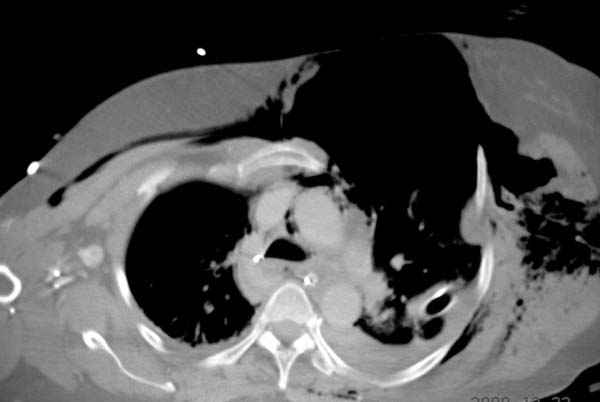

К нам поступила больная 56 лет после автоаварии в бессознательном состоянии, которая срочно заинтубирована в приемном отделении и сделаны необходимые исследования. Данные КТ и рентген показали перелом дистального бедра и Dissociation upper extremity - закрытый отрыв левой верхней конечности на уровне грудинно-ключичного сочленения и множественные переломы ребер.

На поверхности грудной клетки из-за полного разрыва грудной мышцы под кожей заметно биение сердца и след от ремня безопасности. Грудная клетка расширена из-за смещения верхней конечности вверх и латерально. Признаков васкулярного повреждения нет, и из-за отсутствия сознания не смогли определить наличия повреждения нервов.